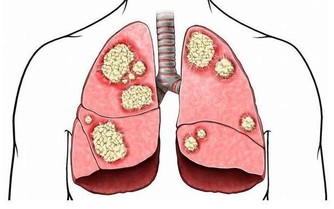

膀胱感染或膀胱癌。疼痛和血尿是膀胱癌的典型症狀,及早發現,治癒的可能性很高。

驗尿能排除細菌感染;如果是膀胱腫瘤,可以通過手術治療,或接受放療和化療。